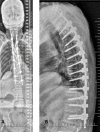

Methods: We report 2 unique cases of distal junctional failure (DJF) with worsening of neurology, secondary to nontraumatic fracture of a lower instrumented vertebra operated for thoracic canal stenosis without deformity. The first case had acute worsening of the Neurology during follow up and on evaluation, the supine CT and MRI scan revealed well decompressed spinal canal, no implant migration to the canal, no screw loosening, or rod failure. Supine sitting radiographs demonstrated DJK with Fracture and the patient underwent extension of fusion till the pelvis with 3-rod construct and interbody fusion, because of the instability at the L1 level.The second case remained neurologically stable for a month and then had an acute onset of back pain, sensory deficit, and urine incontinence. The supine-sitting dynamic radiograph done demonstrated L1 fracture with DJK at D12-L1 levels. The patient was counseled for extension of fusion, which was deferred by the patient.

Results: Patients in our series, had an acute worsening of neurological deficit within a month of posterior spinal fixation. Their supine imaging was almost normal, and the diagnosis of DJK with L1 fracture instability was possible only on a supine-sitting dynamic radiograph. Various factors like obesity, TL kyphosis, osteoporosis, etc. can be the attributing factors for the development of DJK CONCLUSION: A high index of suspicion is required for diagnosing nontraumatic fracture in long-level fusion patients with acute neurological worsening. The supine-sitting dynamic radiograph is an important diagnostic tool for DJF in patients having difficulty standing erect.